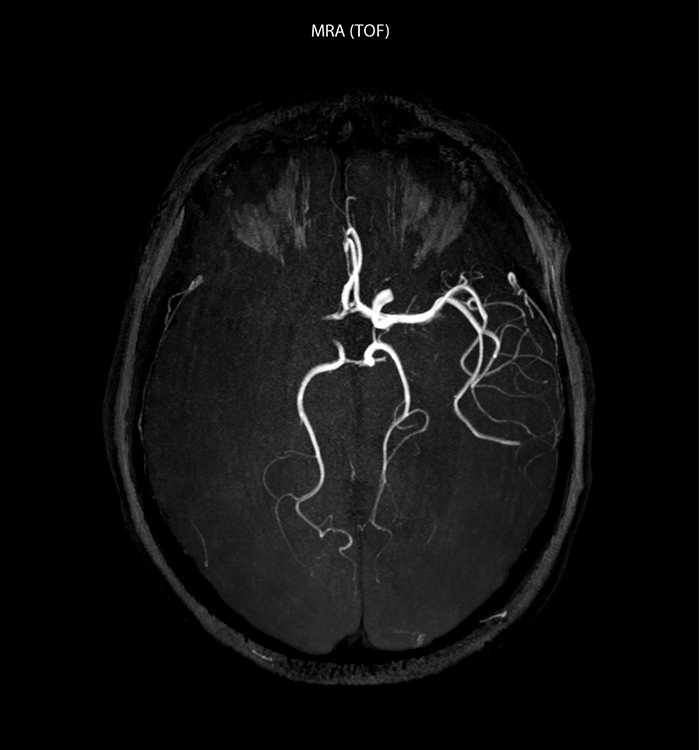

“In France, stroke is usually imaged with MRI, not CT, even for emergency treatment. This is because MRI helps us directly visualize ischemia in the acute phase, but can also help rule out differentials such as MS and hematoma. In addition, we can assess the intracranial and extracranial vessels during the same examination,” says Dr. Savatovsky.

“Ingenia provides great flexibility in the parameters setting. We can tune a sequence the way we want,” says Dr. Savatovsky. “For example, in a stroke exam we use a FLAIR sequence of about two minutes instead of the four-minute FLAIR we use for MS. The diffusion is 30 seconds, the T2*-weighted scan is 30 seconds, the angiography scan time is less than one minute. Ingenia is a great scanner in that situation; even with these fast sequences we can achieve good images with good SNR. When the first sequence tells us that it’s not an ischemic stroke but a hemorrhagic stroke, we may switch to a time-resolved angiography to look for vascular malformations and venous thrombosis.

“Every center is different, but for me the ideal protocol for stroke includes diffusion weighted imaging, FLAIR, and fast susceptibility imaging,” says Dr. Savatovsky. “Our fast susceptibility weighted imaging takes 50 seconds, so it’s as fast as T2*-weighted imaging. It visualizes hemorrhage but also the clots. We also do 3D MR angiography that provides information on cervical and brain vessels. If the patient does not need immediate treatment, or if additional information is needed to decide on treatment, we might also add perfusion imaging and post-contrast T1-weighted imaging.”